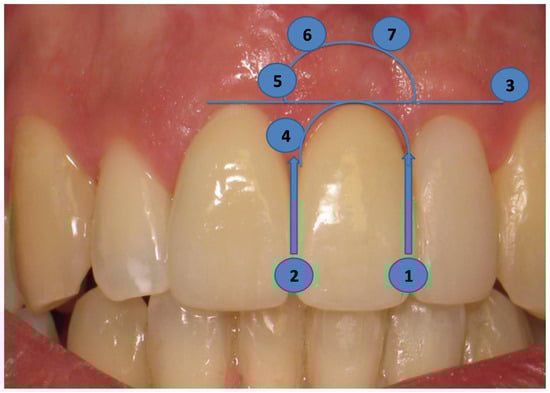

2.4. Long-Term Results of Soft Tissue Esthetic Outcome and Radiographic Evaluation

3.2. PES Assessment